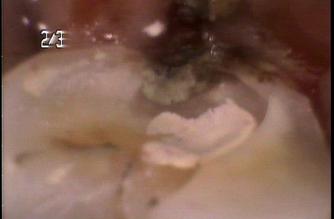

Before

| 処置内容 | 親知らずの抜歯後、歯茎より下に部分にフィットするセラミックを入れる治療 |